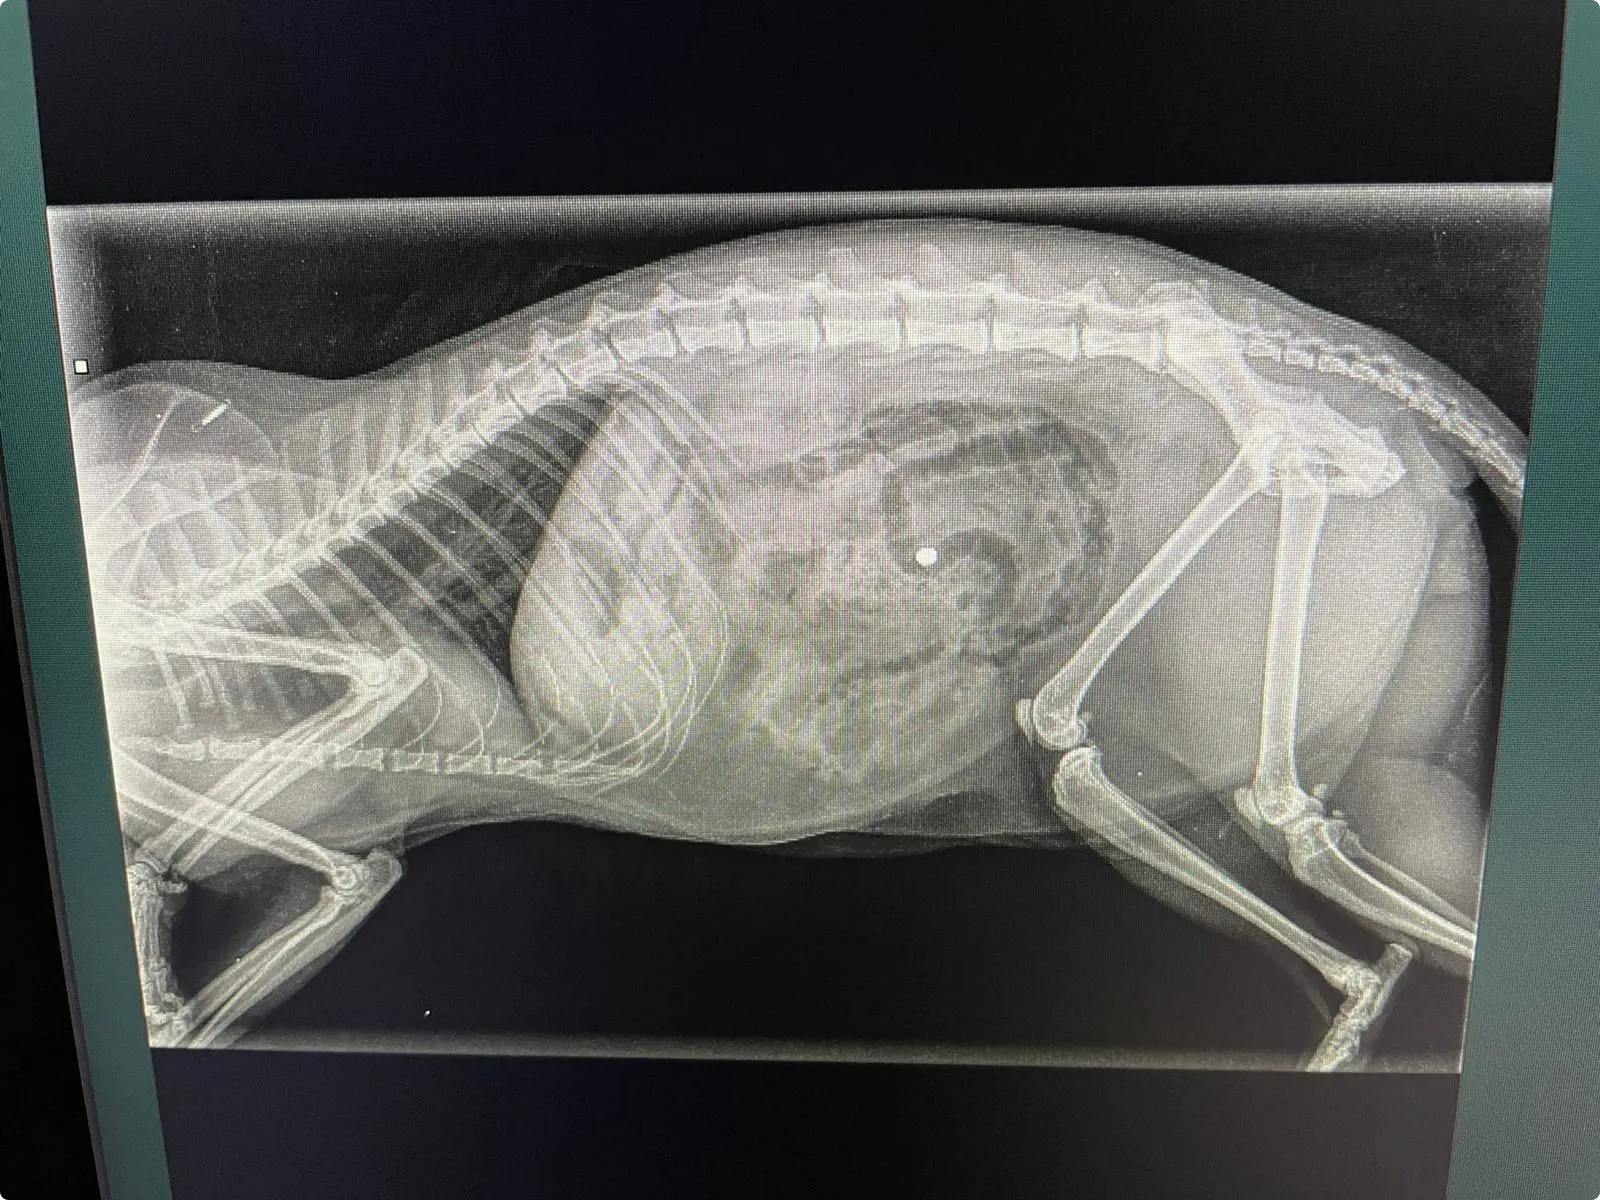

Dierenarts Jos Hermens denkt ook aan een vergiftiging. Maar tijdens het onderzoek ziet hij een gaatje. "Aan de linkerkant. Op de röntgenfoto was het meteen duidelijk te zien", zegt Hermens. Het beestje was beschoten met een luchtbuks. "Het kogeltje is er aan de linkerkant in gegaan en aan de rechterflank in de spieren gestopt."